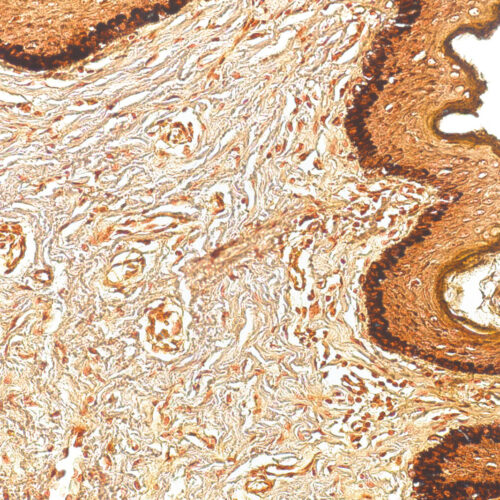

Weigert-Van Gieson kit

Six-reagent kit for staining elastic fibers with a prolonged incubation period. Used for differentiation between elastic tissue, collagen and other types of connective tissue.